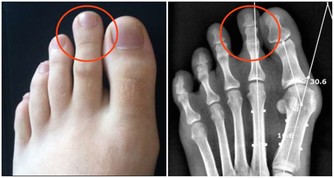

不想被痛風盯上,少吃2種食物,改掉1個壞習慣,自然啥事也沒有

每年體檢報告一拿到手,10個人中總有那麼一兩個人的體檢報告顯示尿酸偏高。

這和現在人們生活飲食習慣息息相關,比如隔天差五吃一頓牛肉火鍋,再過兩天吃頓飯海鮮自助......時間一久就吃出來高尿酸血症。但是有些人並沒有亂吃,飲食很節制,卻也患上了高尿酸血症,這是為什麼呢?

沒亂吃,為何也痛風

可能有人會說,為什麼我沒有胡吃海喝,但還是會痛風?

正常情況下,人體每天生成與排出的尿酸保持著平衡。尿酸升高有兩個方面的因素:一是產生的多,二是排泄的少。

有些人外源性尿酸不多,但內源性尿酸多,也可能導致痛風。

所謂內源性尿酸,是人體代謝過程中自行產生的。當體內嘌呤代謝紊亂,或惡性腫瘤等疾病患者因放化療使腫瘤細胞大量破壞分解,也會導致血尿酸水平的急劇上升。